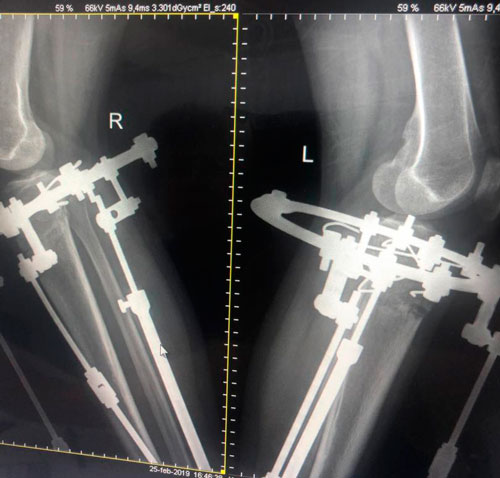

в процессе работы

рентген в 60 дней.

Планируем снятие аппаратов в 75 дней.